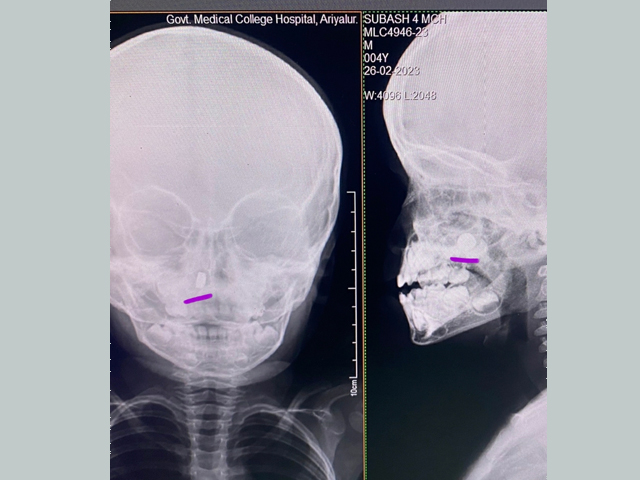

We are providing 24X7 emergency care services for Ear Nose Throat and Neck emergency like trauma with Ear / Nose Bleeding, cut throat injury, Acute airway obstruction with stridor, Foreign Bodies in Ear, Nose, Food passage and Airway.